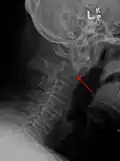

Type 3 odontoid fracture

Type 2 dens fracture